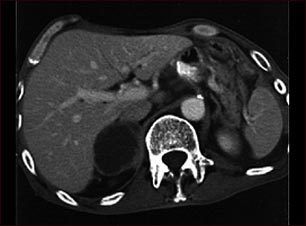

Metástasis suprarrenal -TC

TC de la parte superior del abdomen que muestra una metástasis suprarrenal (diseminación del tumor a la glándula suprarrenal, encima del riñón) en una persona con cáncer de pulmón.